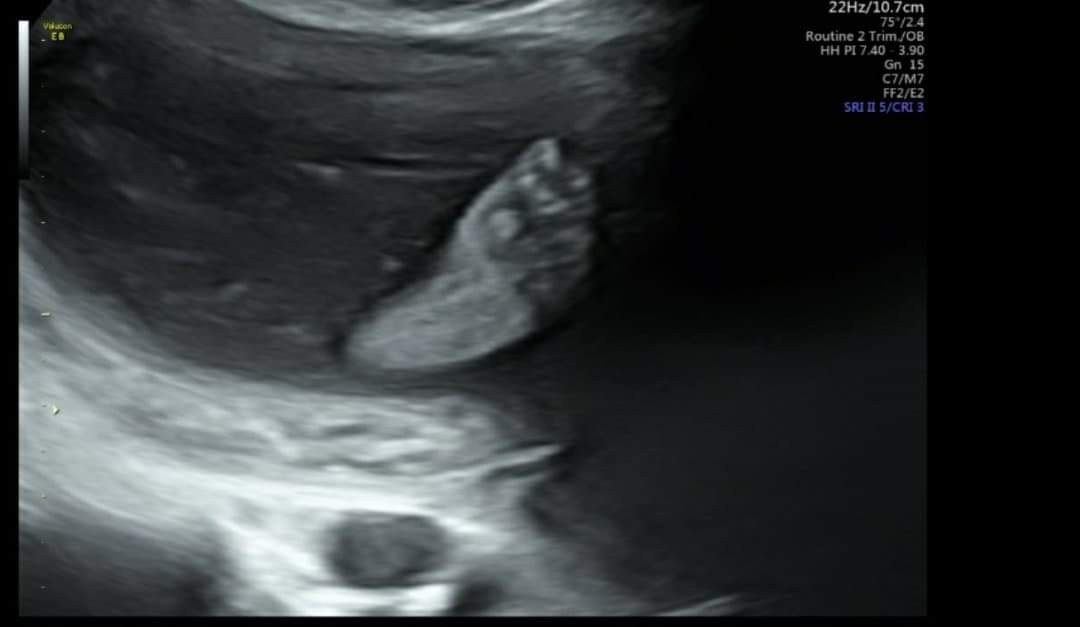

My jesteśmy po polowkowych 🥰

456 g moja czupakabra waży 🥰

Wszelkie wady wykluczone ❤

mam taką fotkę dwóch stópek obok siebie 😍